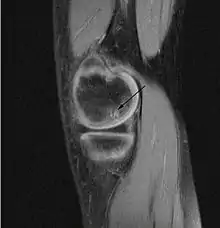

يمكن استخدام الأشعة السينية أو الأشعة المقطعية أو التصوير بالرنين المغناطيسي لتشخيص ما إذ كان المريض يعاني من التهاب العظم والغضروف السالخ، فهي تظهر نخر العظم تحت الغضروف أو تشكل شظايا رخوة أو كلاهما،[25] وفي بعض الأحيان تستخدم أشعة الطب النووي العظمي لتقييم درجة الترخي داخل المفصل.[26]

ويصنف تطور المرض في مراحل، هنالك نوعان رئيسيان من التصنيف مستخدم: يحدد واحد منهما عن طريق التشخيص بالتصوير بالرنين المغناطيسي بينما يحدد الأخر عن طريق التنظير، ومع ذلك تمثل كلا المرحلتين التقدم الطبيعي للحالة المرضية من مرض (التهاب العظم والغضروف السالخ)، في حين يعد التصنيف بالمنظار في العظام والغضاريف المعيار كما صنف اندروسون التصوير بالرنين المغناطيسي هو الشكل الرئيسي المستخدم في هذا المقال [29]، وتعد المرحلتين الأولى والثانية مراحل مرضية مستقرة، بينما هنالك مراحل مصنفة تعد غير مستقرة الا وهي المرحلتان الثالثة والرابعة التي تسمح للسائل الغضروفي والسائل الزليلي ان يكون بين الأجزاء والعظام.

'مرحلة أندرسون التصوير بالرنين المغناطيسي للكشف عن مرض التهاب العظام السالخ (التهاب عظمي غضروفي)' [30]